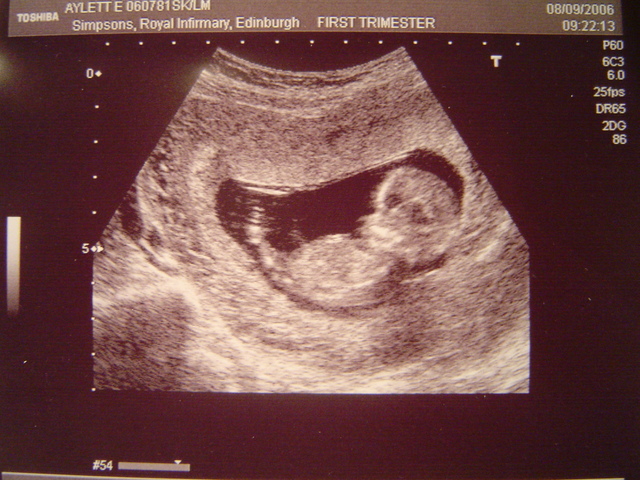

6 Weeks

The heartbeat of the baby is able to be seen with an ultrasound. The nose, mouth and ears are begginning to form. The baby is considered to be a embryo. At this stage you cannot feel your baby kicking. Your baby will start kicking when your at at week 16 through week 24. The baby cannot hear you yet even though the ears are developing. The baby can hear you singing or talking when you are 16 weeks pregnant.